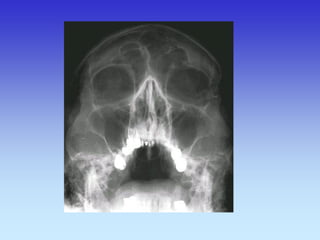

SINUSI PA snimka

1.Nosna pregrada

2.Frontalni sinus

3.Maksilarni sinus

4.Etmoidni sinus

SNIMKA SINUSA